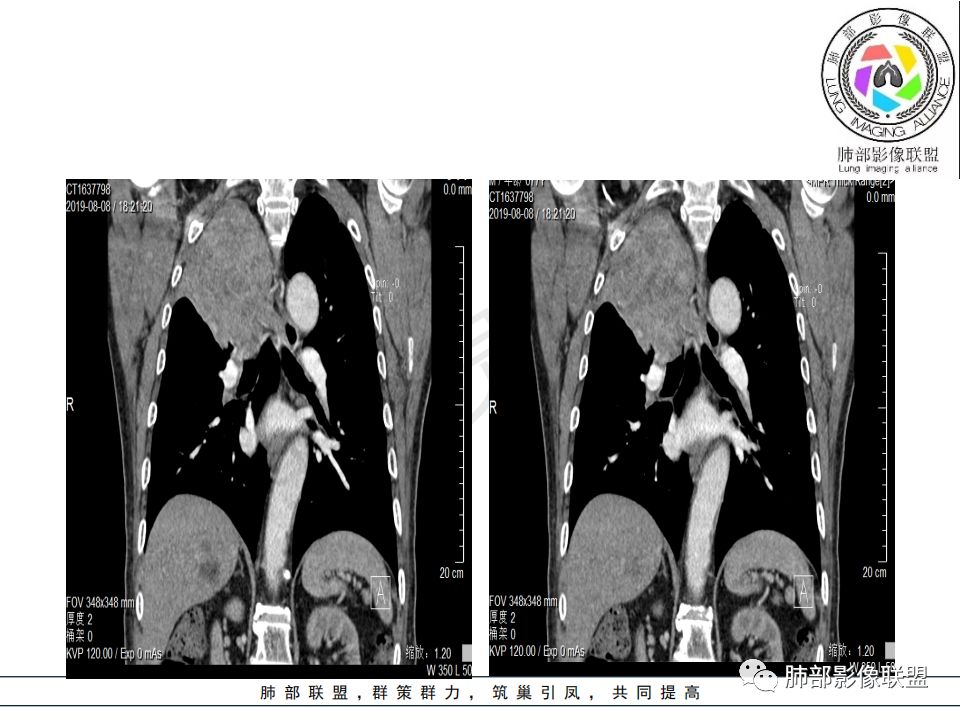

从强化情况和冠状位看主要还是从外向内的一个肿块,有不张,但不张范围不大,近端支气管堵塞,考虑腺癌或类癌(原发或转移都可能),鉴别鳞癌。

@曹坤,河北保定清苑区人民医院ct室 肿块大,阻塞和不张范围小,强化这么大肿块没有明显坏死,鳞癌这样相对少见了

@刘鋆(福州长乐区医院)影像科 转移啊,腔外都在生长,部分通过支气管壁进入腔内

@刘鋆(福州长乐区医院)影像科 先转移生长到外面,然后进入腔内生长,也是外朝内一种,与平时那种外朝内生长逐渐侵犯近端气管没有太多区别,只不过这个是转移而已。

病理结果:腺癌,考虑来源消化道

1.右肺上叶较大块影,密度不均,轻度强化并见低密度区,所属支气管截断并腔内突入,是符合肺鳞癌的影像学特征和生物学行为的。

2.胃癌常会首先胃旁淋巴结、腹主动脉淋巴结转移,肝脏血行转移,以及双肺多发转移,本例孤立右肺上叶病灶巨大,多有不符。

3.胃癌多血供,患者肺内病灶轻度强化。